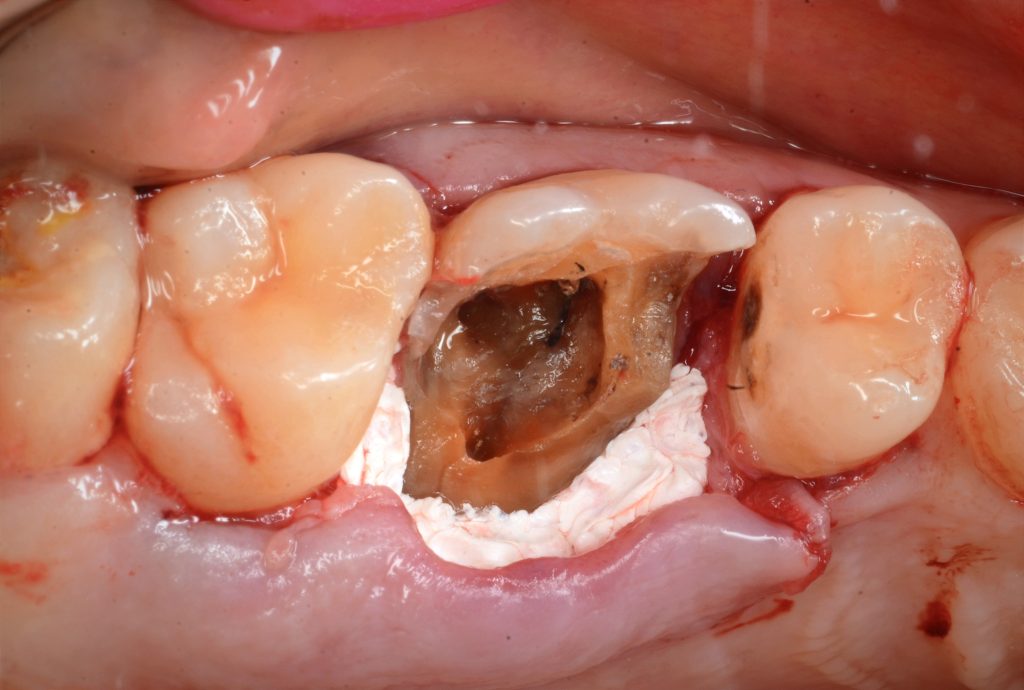

After deep margin elevation

Take one month for healling

R.c.t done